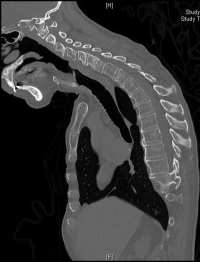

A cervical deformity shows itself as an abnormal curve or angulation in the normally smoothly curved neck. The cause is degenerative facet or disc disease at multiple levels.

The normal neck alignment in the front to back view should be straight up and down and from the side, should display a backwards curve called a lordosis. The lordosis is caused by the trapezoidal shape of the discs. The bodies of the vertebra are square and stacking them up on top of each other without the discs and facets would form a straight tower.

If the discs or facets break down (and they normally do), but break down asymmetrically, an abnormal alignment occurs. If this breakdown occurs at only one level, the malalignment rarely causes an abnormal curve. If this breakdown occurs at multiple levels, a deformity of the spine will result. One level’s abnormal angulation will add to the abnormal angulation above and below to cause a scoliosis or a cervical kyphosis (a loss of curve in the neck compared to the natural lordosis). These conditions appear as a curvature of the neck and are neck deformities that cause neck pain and instability.